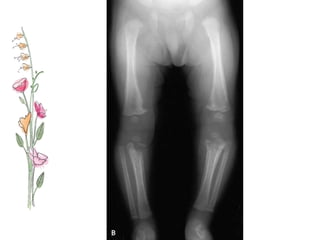

Bone lesions

• During first six months – osteochondritis of long bones

(upp. end of tibia, distal end of radius & ulna)

• Child presents with severe pain, tenderness while

handling with consequent loss of movements  syphilitic

pseudo paralysis.

• Wimberger’s sign- loss of density on the medial side of

upper end of tibia .

• Tibia is most frequently involved, thickening of middle

third causes anterior bowing ‘Sabre tibia’